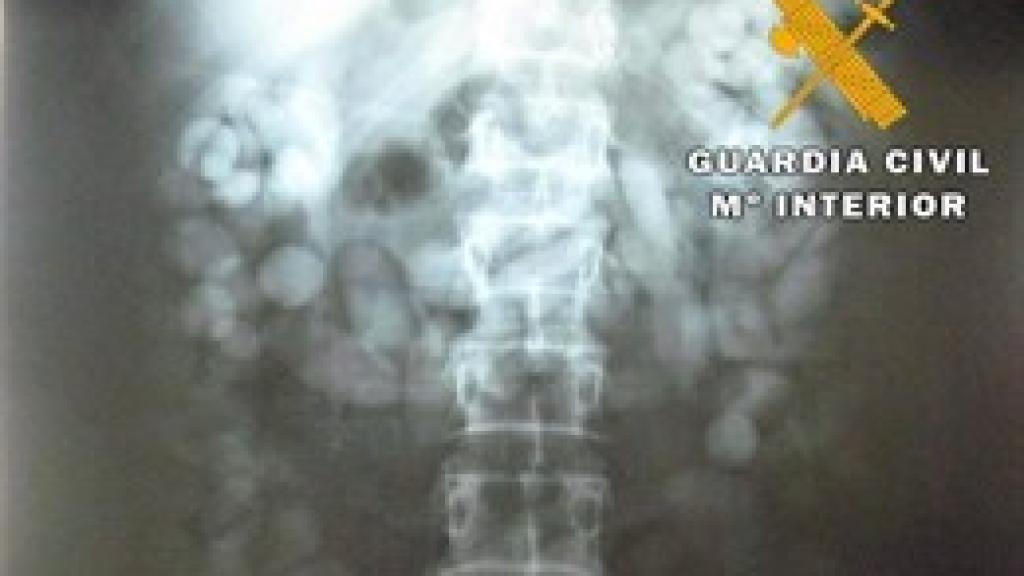

Radiografía del torso del hombre detenido

Tras ser sometido a la exploración radiológica, se detectaron numerosos cuerpos extraños en el interior del aparato digestivo de esta persona, siendo expulsados más tarde y dando un total de 216 bellotas con un peso de 1,511 kilos de hachís.